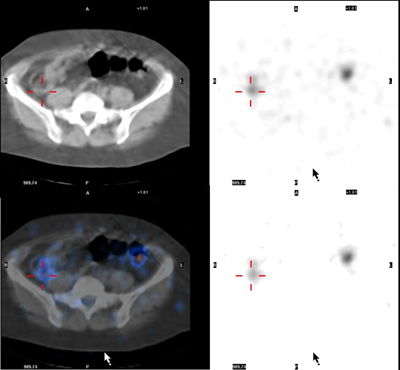

State-of-the-art imaging allows Nuclear Medicine and CT images to be taken during the same scan. By superimposing these images, we can more accurately see the location of any areas of disease.